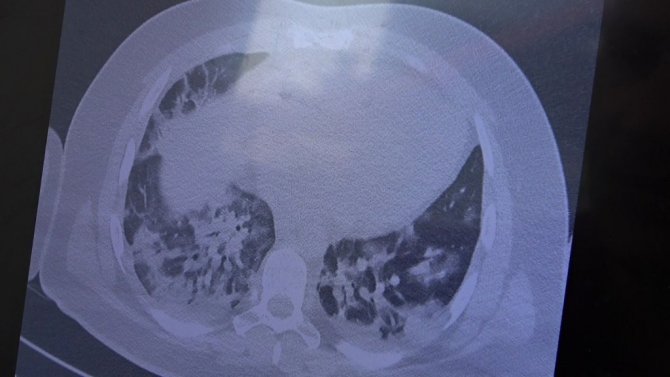

Gençlerin akciğer tomografilerini inceleyen Özkaya, "İki vaka örneği hakkında bilgi vermek istiyorum. İnsanlara bu işin bitmediğini anlatmamız lazım. 30 yaşında aşı olmamış bir hastamızın filminde çok yaygın akciğer hasarı var. Şu an kendisi yoğun bakımda tedavi alıyor. Öte yandan 25 yaşında bir hastamız var. İki doz kovid aşısını da olmamış. Ciddi akciğer tutulumları var. Çok ciddi solunum sıkıntısı ile kovid servisinde yatıyor. Şu an hasta profilimizin büyük bir kısmını bu durum oluşturuyor" ifadelerini kullandı.